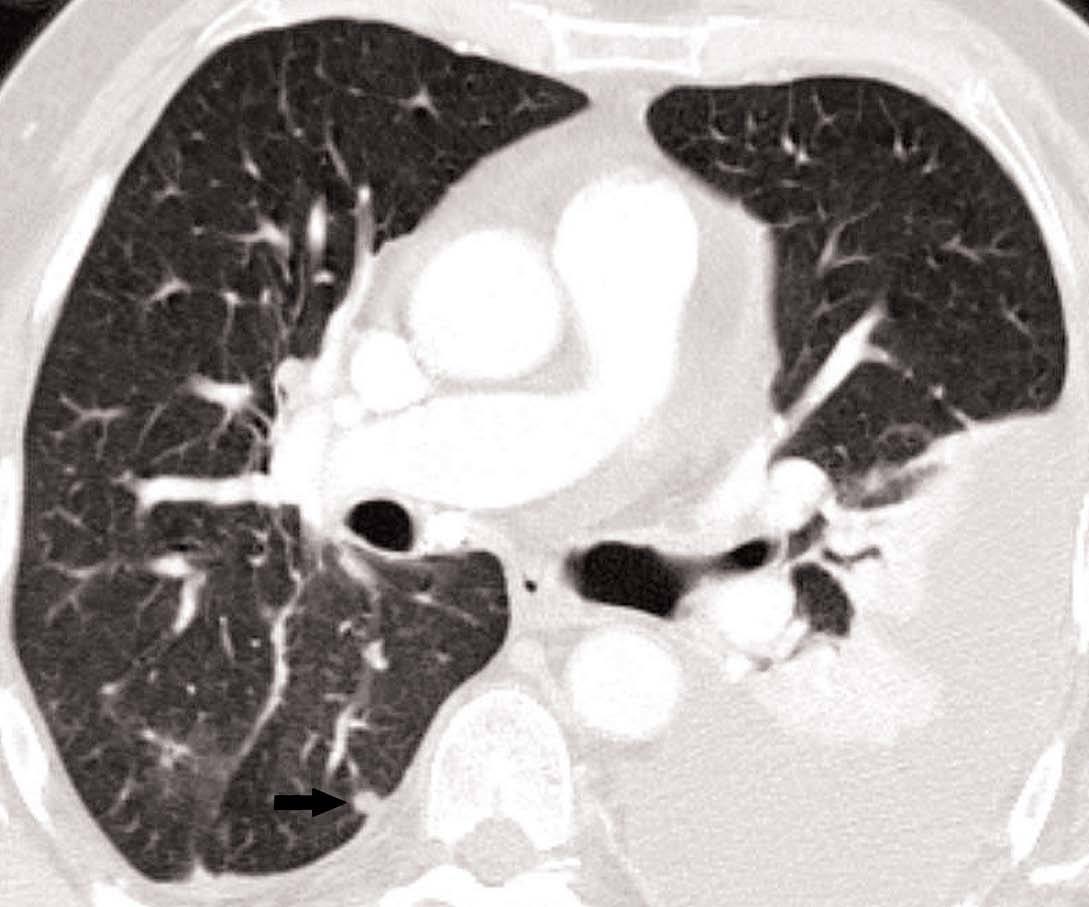

Fig. 11.--N2. (A) Corte axial de tomografía computarizada (TC) con contraste. Nódulo heterogéneo en el segmento 6 del lóbulo inferior derecho con infiltración de la vena pulmonar inferior (flecha). (B) En la reconstrucción de volumen se ponen de manifiesto la infiltración tumoral de la vena pulmonar (flecha negra), la adenopatía hiliar (asterisco) y una adenopatía calcificada lobar superior derecha (flecha blanca).

Fig. 12.--Estaciones ganglionares para la estadificación del cáncer de pulmón. Las reconstrucciones multiplanares (MPR) son de gran ayuda para precisar los territorios ganglionares afectos. Correlación de los territorios ganglionares entre el mapa ganglionar de Mountain y Dressler y una reconstrucción coronal de un paciente con afectación adenopática mediastínica e hiliar bilateral. (A y B) Ganglios mediastínicos superiores e inferiores e hiliares. (C y D) Ganglios aórticos. AP: arteria pulmonar. Ao: aorta.